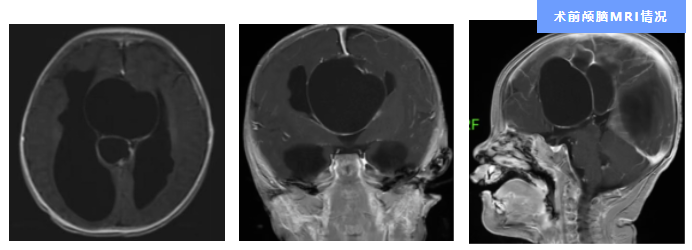

神经外科三区主任周向阳博士团队接诊了小王。通过影像检查,发现小王的颅脑中线区有多发蛛网膜囊肿伴脑积水。

“蛛网膜囊肿不会变成肿瘤、也没有侵袭性,绝大多数的不会导致任何症状。但少数的囊肿会生长占据过多的颅腔空间从而引发一系列并发症,需要通过手术治疗。小王尚且只有3个月大,囊肿就显著生长、压迫到了正常脑组织,甚至引发癫痫,这种情况是比较少见的。”周向阳说。

小王的病情不仅少见,还是神经外科三区开科以来收治患者中年龄最小的孩子。生长发育未完全的颅脑,让麻醉、手术施行、创口控制、术后护理都成了医疗团队必须逐个击破难题和挑战。团队迎难而上,术前邀请医院麻醉科、儿科、有关医技科室及临床营养科专家参与会诊,根据小王的病情及身体状况制定手术方案,并提出了“术前到术后全程管理”的诊疗模式,以更好地为小王“护航”。团队与家属充分沟通治疗事宜,细致、专业的方案与医护人员温和、耐心的态度缓解了家属的焦虑,也赢得了他们对手术的充分信任与支持。